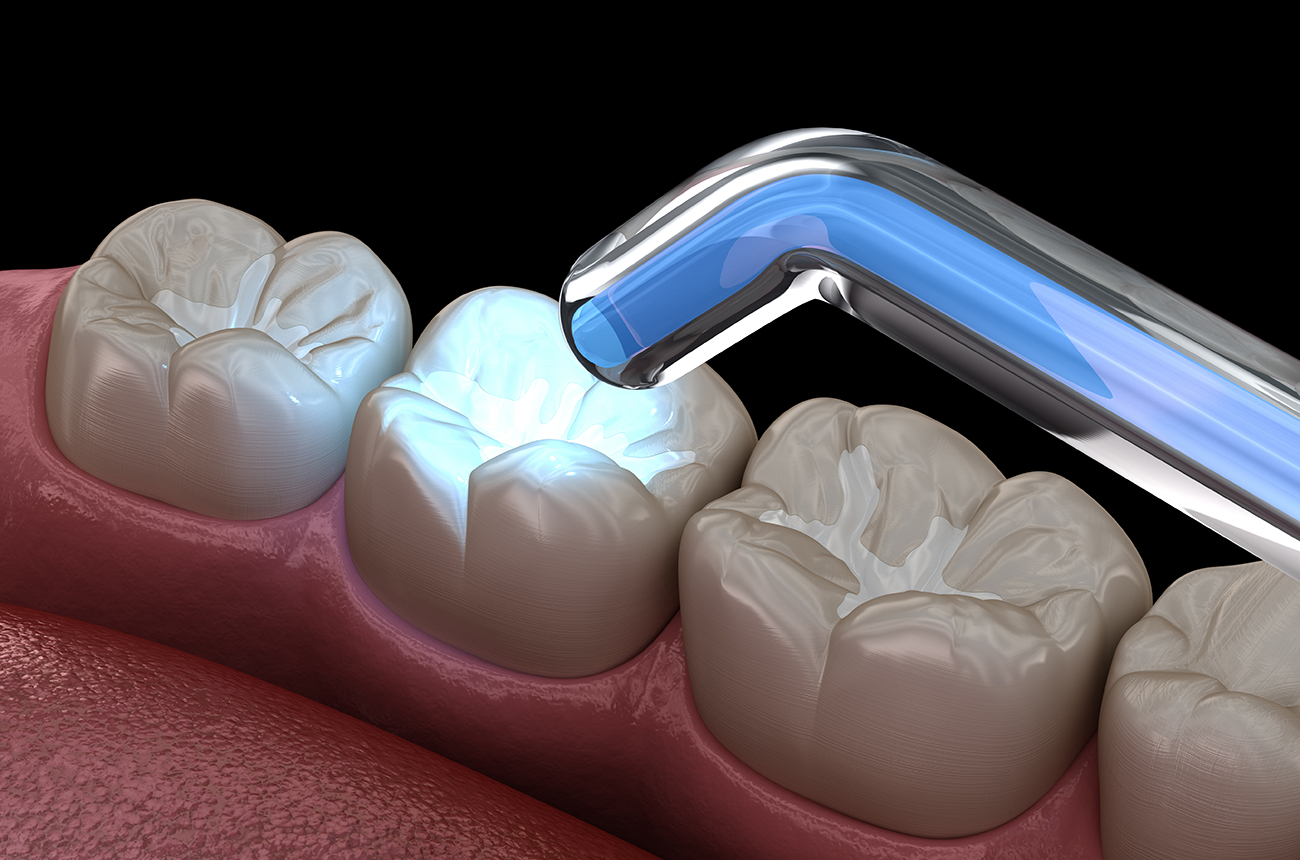

装置を使っての矯正治療

歯並び、かみ合わせ、骨格の状態を細かくチェックし、お子さんに合わせた装置を用いて矯正治療を行います。